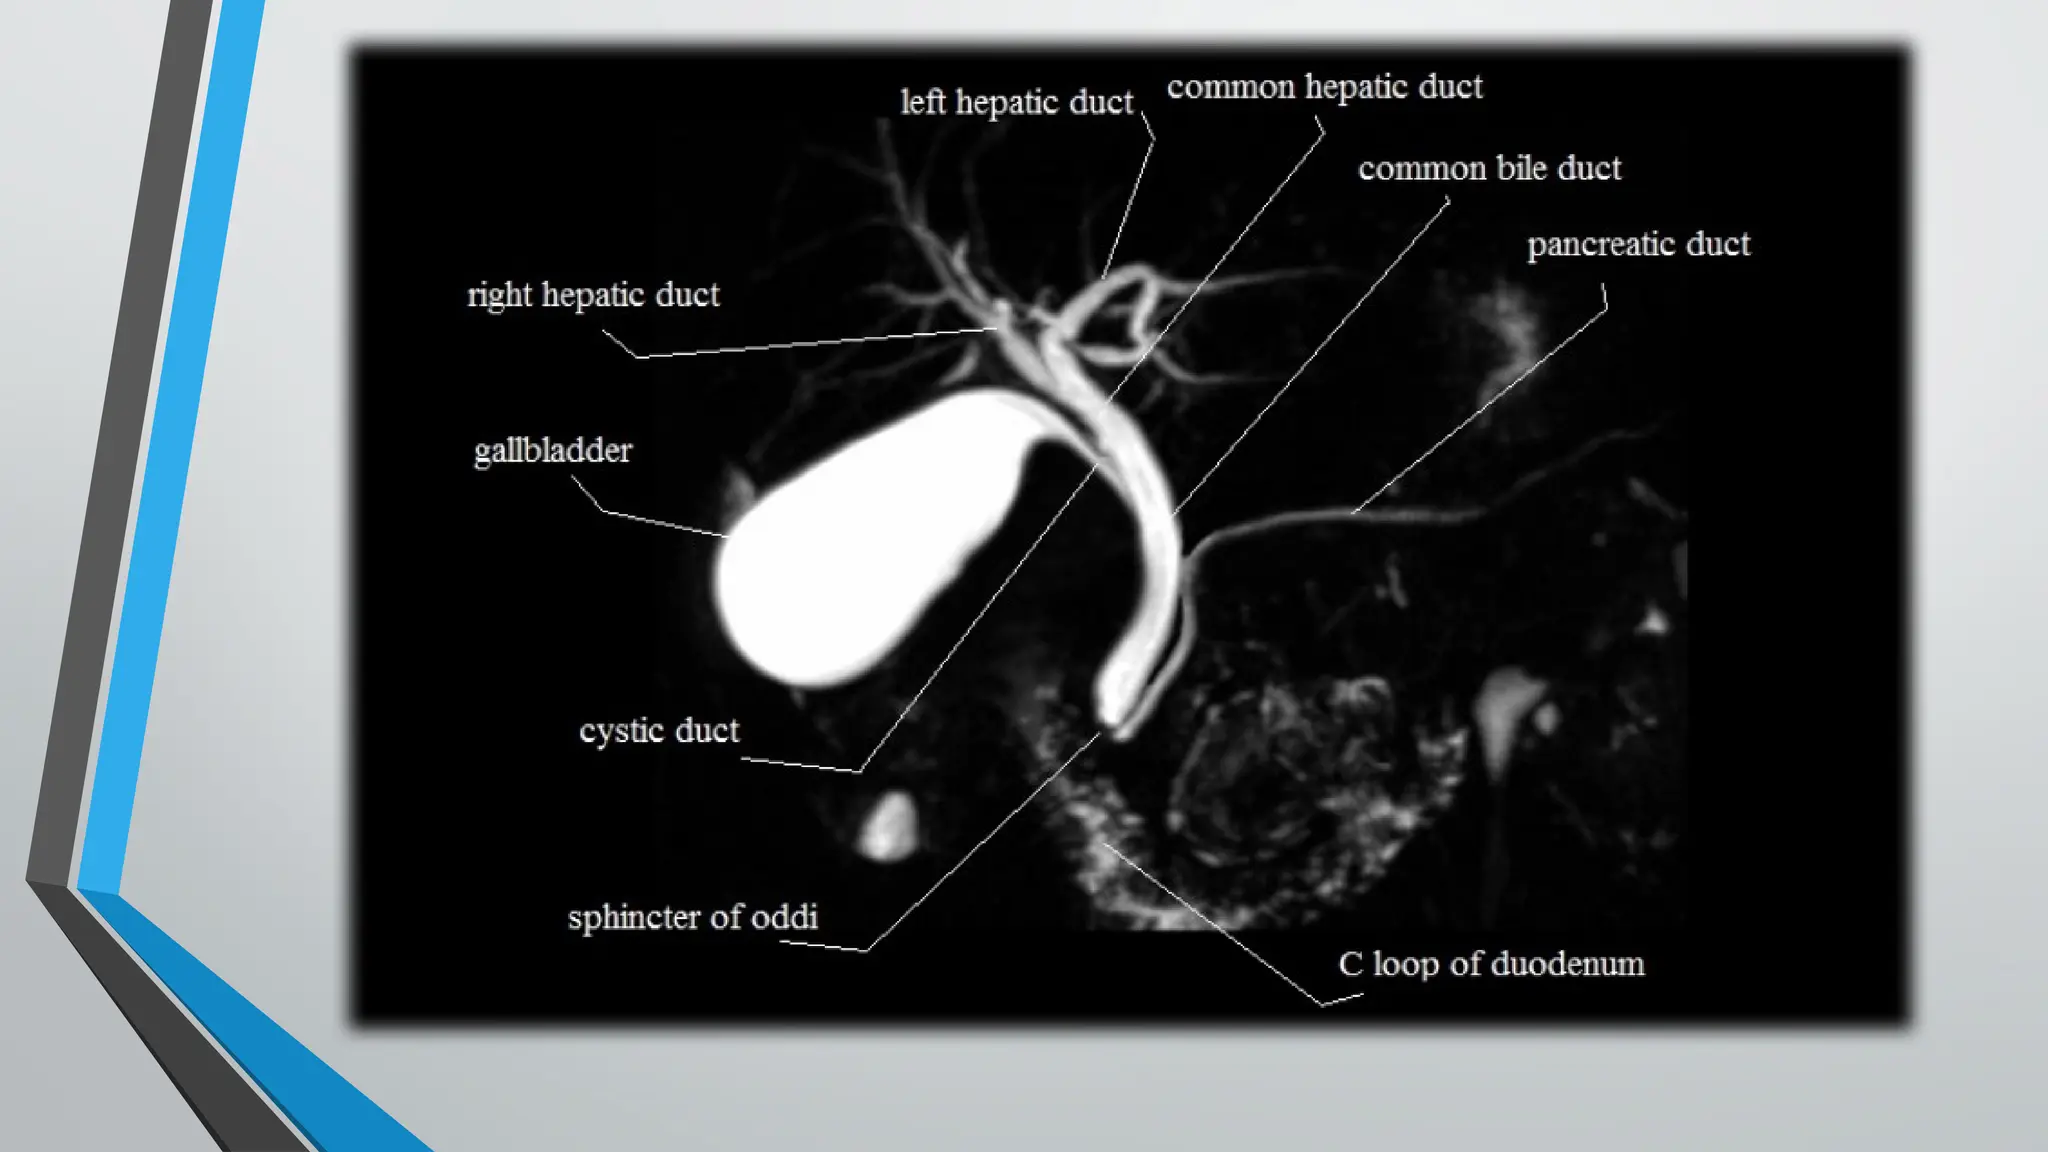

• MAGNETIC resonance cholangiopancreatography (MRCP) is a

radiologic technique that produces images of the

pancreatobiliary tree.

• Body fluids (bile and pancreatic secretions) have high signal

intensity on heavily T2-weighted MR sequences

therefore, appear white. --Background tissues generate little

signal appear dark.